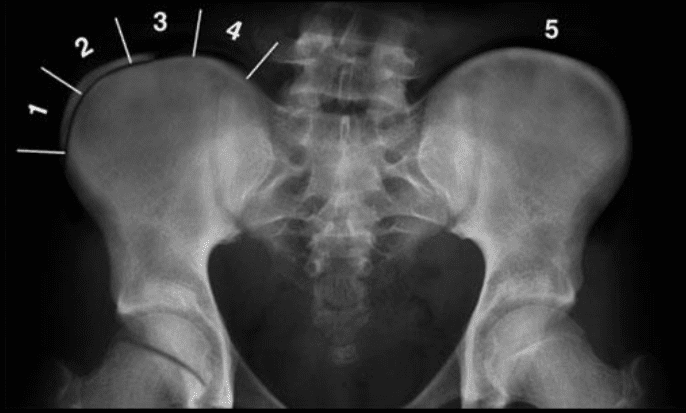

Studji dwar l-Immaġini

L-immaġini f'mard deġenerattiv tad-diska tintuża prinċipalment biex tiddeskrivi relazzjonijiet anatomiċi u karatteristiċi morfoloġiċi tad-diski affettwati, li għandha valur terapewtiku kbir fit-teħid ta 'deċiżjonijiet futuri għal għażliet ta' trattament. Kwalunkwe metodu ta 'immaġini, bħal radjografija sempliċi, CT, jew MRI, jista' jipprovdi informazzjoni utli. Madankollu, kawża sottostanti tista 'tinstab biss fi 15% tal-pazjenti billi l-ebda bidliet radjoloġiċi ċari ma huma viżibbli f'mard deġenerattiv tad-diska fin-nuqqas ta' ħernja tad-diska u defiċit newroloġiku. Barra minn hekk, m'hemm l-ebda korrelazzjoni bejn il-bidliet anatomiċi li dehru fuq l-immaġini u s-severità tas-sintomi, għalkemm hemm korrelazzjonijiet bejn in-numru ta 'osteofiti u s-severità ta' uġigħ fid-dahar. Bidliet deġenerattivi fir-radjografija jistgħu jidhru wkoll f'nies bla sintomi li jwasslu għal diffikultà biex jikkonformaw ir-rilevanza klinika u meta tibda l-kura. ("Marda tad-Diska Deġenerattiva" Fiżjopedja)

Ir-Radjografija

Din ir-radjografija ċervikali sempliċi rħisa u disponibbli b'mod wiesa 'tista' tagħti informazzjoni importanti dwar id-deformitajiet, l-allinjament, u bidliet deġenerattivi taż-żaqq. Sabiex tiġi ddeterminata l-preżenza ta 'instabilità ta' l-ispina u bilanċ sagittali, għandhom isiru studji ta 'flessjoni dinamika jew estensjoni.